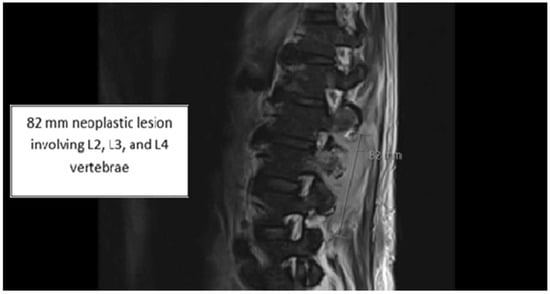

2. Case